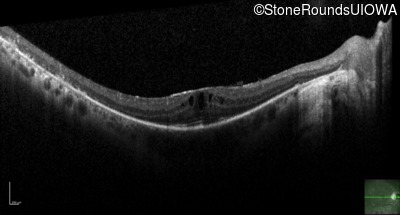

Optical Coherence Tomography - Right - 20/20

Exemplar / OCT Stack

OCT Stack